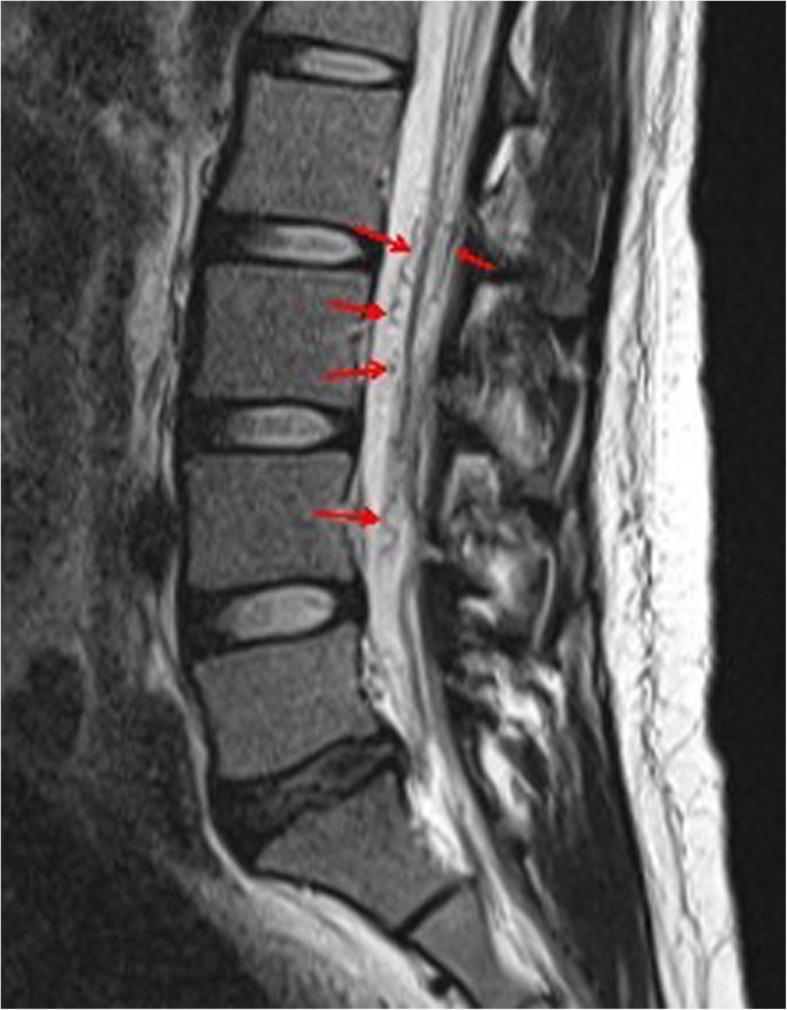

A 27-year-old parturient with pulmonary hemorrhage was admitted to our tertiary perinatal center. She was first diagnosed with HHT and a cesarean delivery using spinal anesthesia at 37 weeks of gestation was initially planned. However, magnetic resonance imaging (MRI) at 32 weeks of gestation revealed spinal AVM ranging from the thoracic to the lumbar levels. Thus, elective cesarean delivery under general anesthesia was planned. The parturient had an uneventful perioperative course.

一名27岁的患有肺出血的产妇被收治到我们的三级围产期中心。她最初被诊断为HHT,最初计划在妊娠37周时采用脊髓麻醉进行剖宫产。然而,妊娠32周时的磁共振成像(MRI)显示脊髓AVM范围从胸段到腰段。因此,计划在全身麻醉下进行择期剖宫产。该产妇围手术期过程顺利。